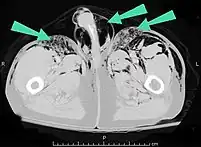

An abdominal CT scan of a patient with subcutaneous emphysema (arrows) | |